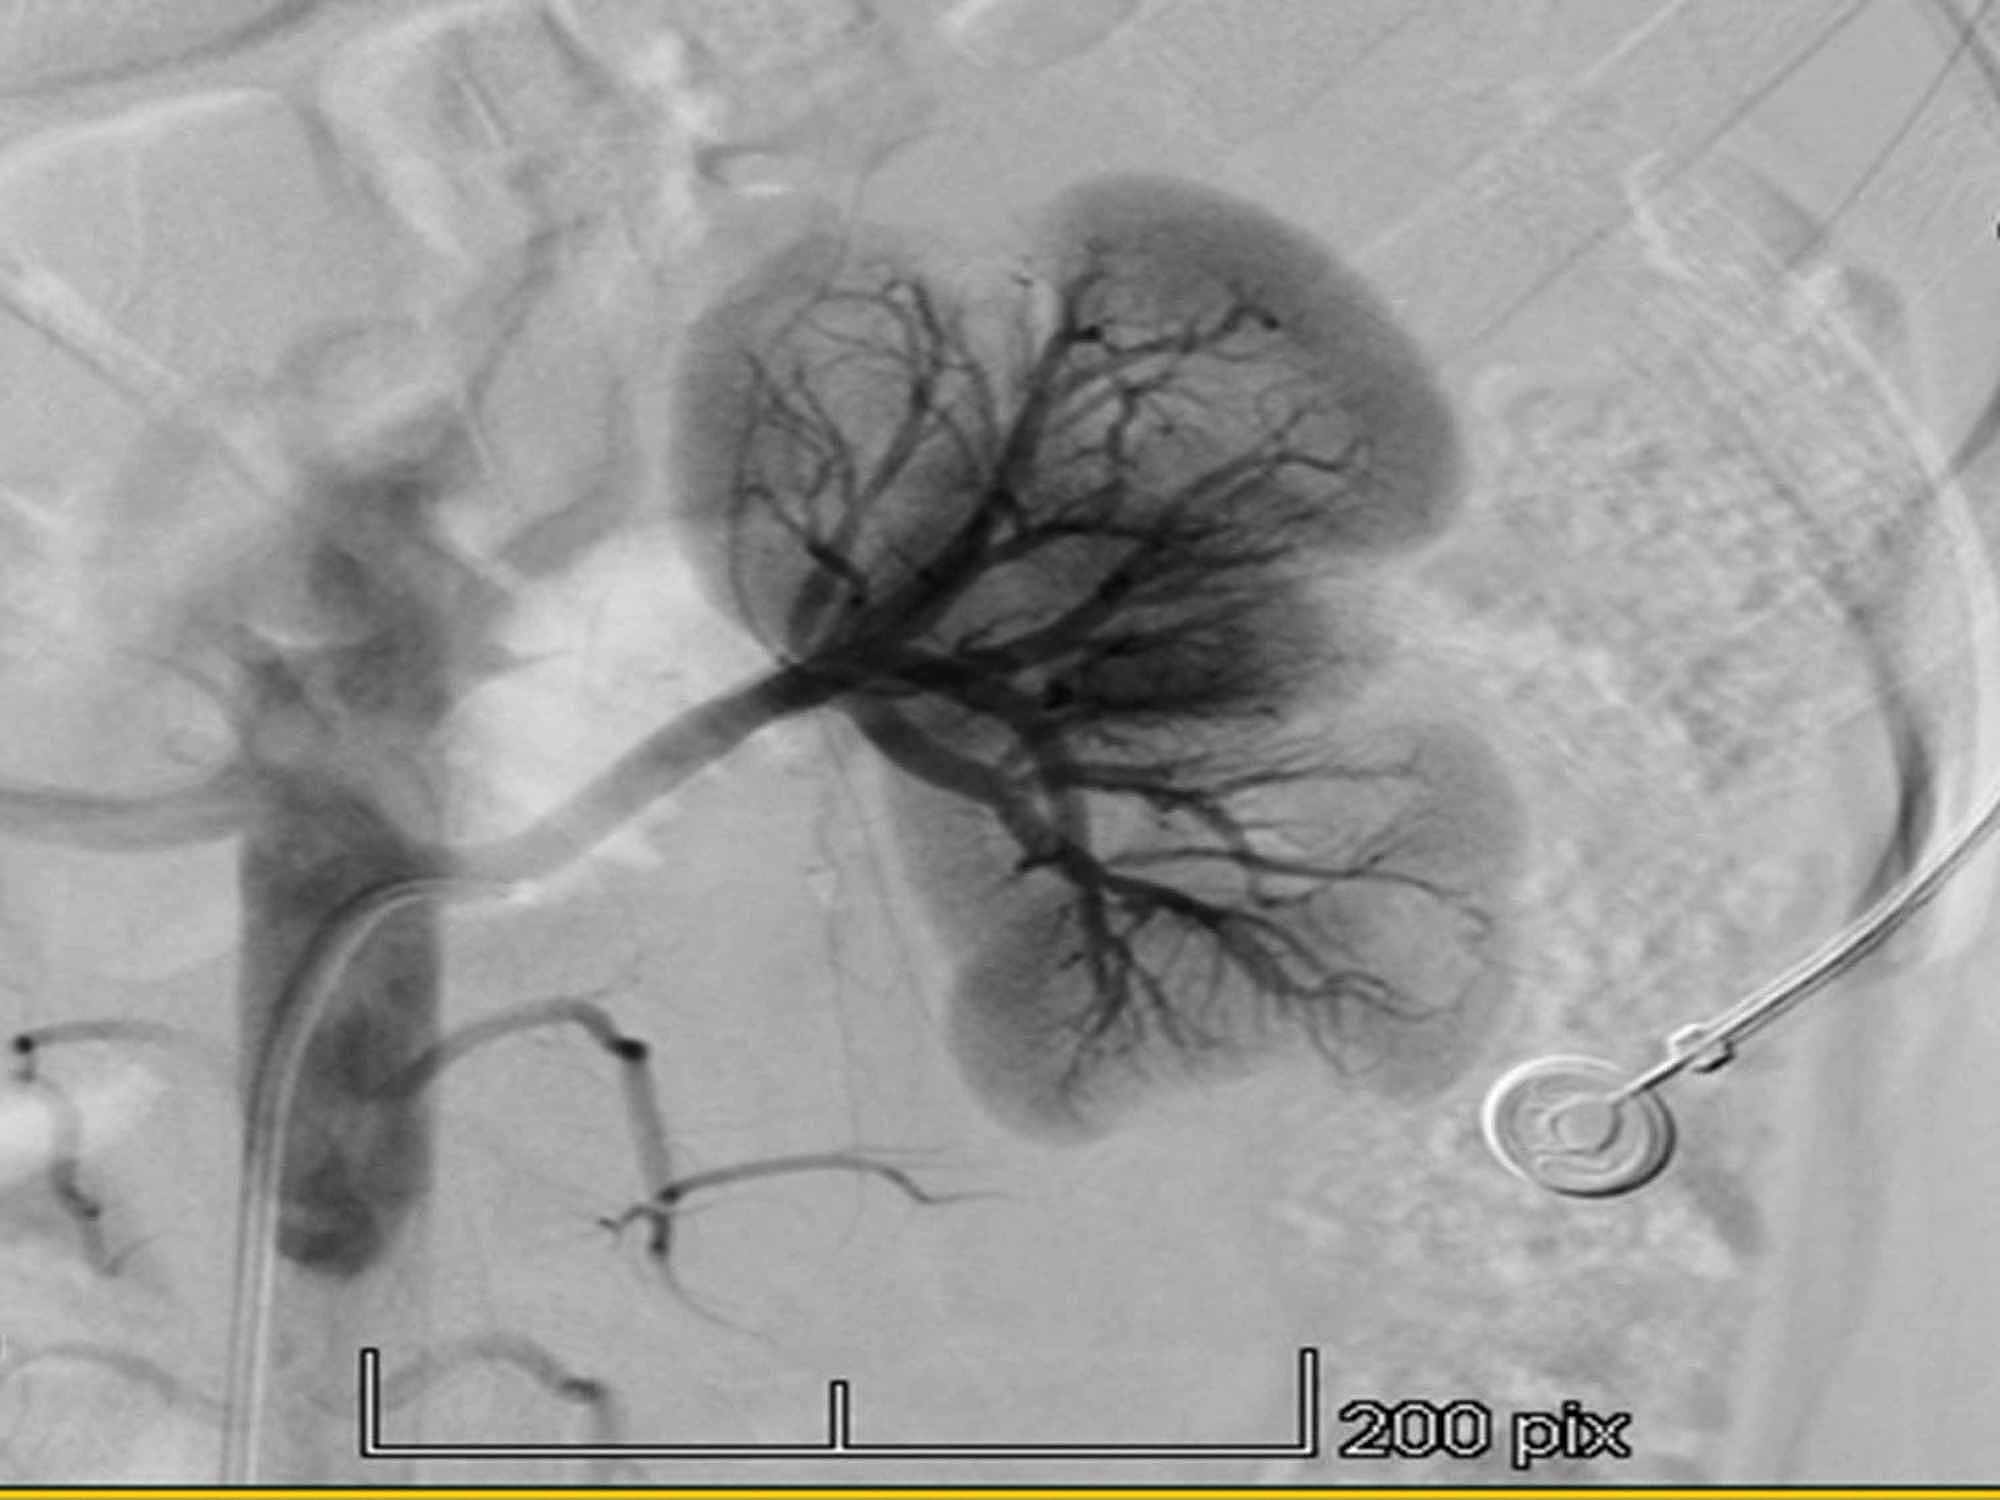

Figure 1 from Can Nutcracker Syndrome cause secondary hypertension? Two

Figure 1 from Can Nutcracker Syndrome cause secondary hypertension? Two Nutcracker Syndrome And Hypertension nutcracker syndrome is the compression of your left renal (kidney) vein, usually between your abdominal aorta and superior. the orthostatic proteinuria noted in some patients with nutcracker syndrome may be caused by positionally or posturally induced. nutcracker syndrome (ncs) describes left renal vein compression between the superior mesenteric artery and the aorta. nutcracker syndrome (ncs) is. Nutcracker Syndrome And Hypertension.